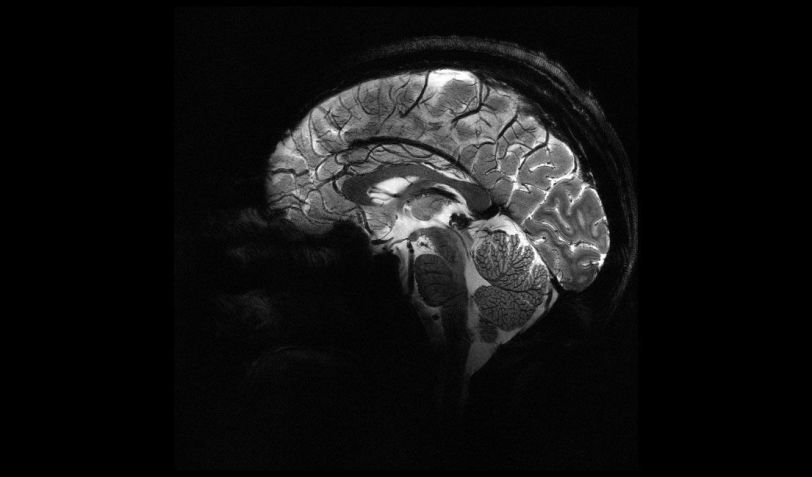

A Comissão de Energia Atômica da França (CEA), compartilhou, na terça-feira (2), imagens inéditas de alta precisão do cérebro humano, realizadas através da máquina de ressonância "mais poderosa do mundo". A descoberta pode ser importante para detectar doenças neurodegenerativas como o Alzheimer e Parkinson.

As novas imagens são fruto de mais de 20 anos de pesquisa e desenvolvimento sobre o scanner Iseult, atualmente considerado como o aparelho de ressonância magnética mais poderoso do mundo, possuindo uma intensidade de campo magnético de 11,7 teslas, maior do que aparelhos normalmente utilizados em hospitais, que chegam no máximo a três teslas.

O objetivo da nova máquina é estudar cérebros humanos saudáveis e doentes utilizando a alta resolução como apoio, que permitirá descobrir novos detalhes relacionados à anatomia, conexões e atividade do cérebro humano.